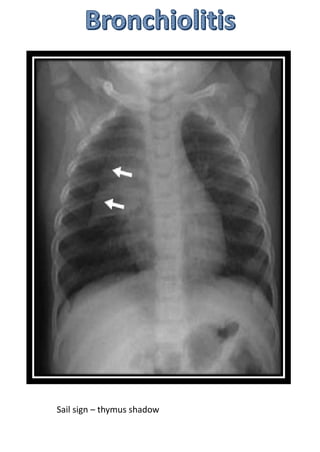

Sail sign – thymus shadow

Hyperinflated lungs: increased radiolucency of

lungs

Flattening of domes of diaphragm

Pulmonary infiltrates

Segmental collapse